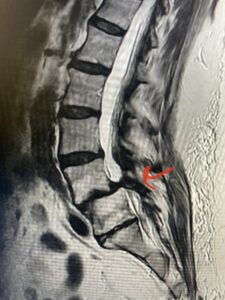

Fig 1: Sagittal T2-weighted lumbar MRI demonstrating grade 1-2 spondylolisthesis L4-5 with severe stenosis (red arrow)

Another patient is a 62 year-old female with progressive low back pain and right leg pain and numbness that radiates to the top of her foot. She tried physical therapy and epidural injections. MRI demonstrated severe L3-4 stenosis and a grade 1 spondylolisthesis (Fig 4). There was L5-S1 and L4-5 disc collapse with modic end-plate changes. Biomechanically because of the significant degeneration of these disc spaces which stiffened the L4-S1 segment more stress was placed on the L3-4 segment, resulting in significant premature degeneration and compensatory stenosis and segmental instability. The MRI also showed pathologically, because of the slip, the L3 inferior processes were more anteriorly oriented and hence contributing to the majority of the lumbar canal compromise. Note the more sagittally-oriented facets in this case compared to the prior case (Fig 5). The patient underwent a decompressive laminectomy with attention of removing the inferior processes of L3 to fully decompress the canal. We also performed an L3-4 fusion with instrumentation (Fig 6). The patient had an uneventful postoperative course with improvement of leg pain. Of note with relief of the disabling leg pain patients are generally very happy. Patients can often manage their low back pain; it is the leg pain that they just can’t tolerate.